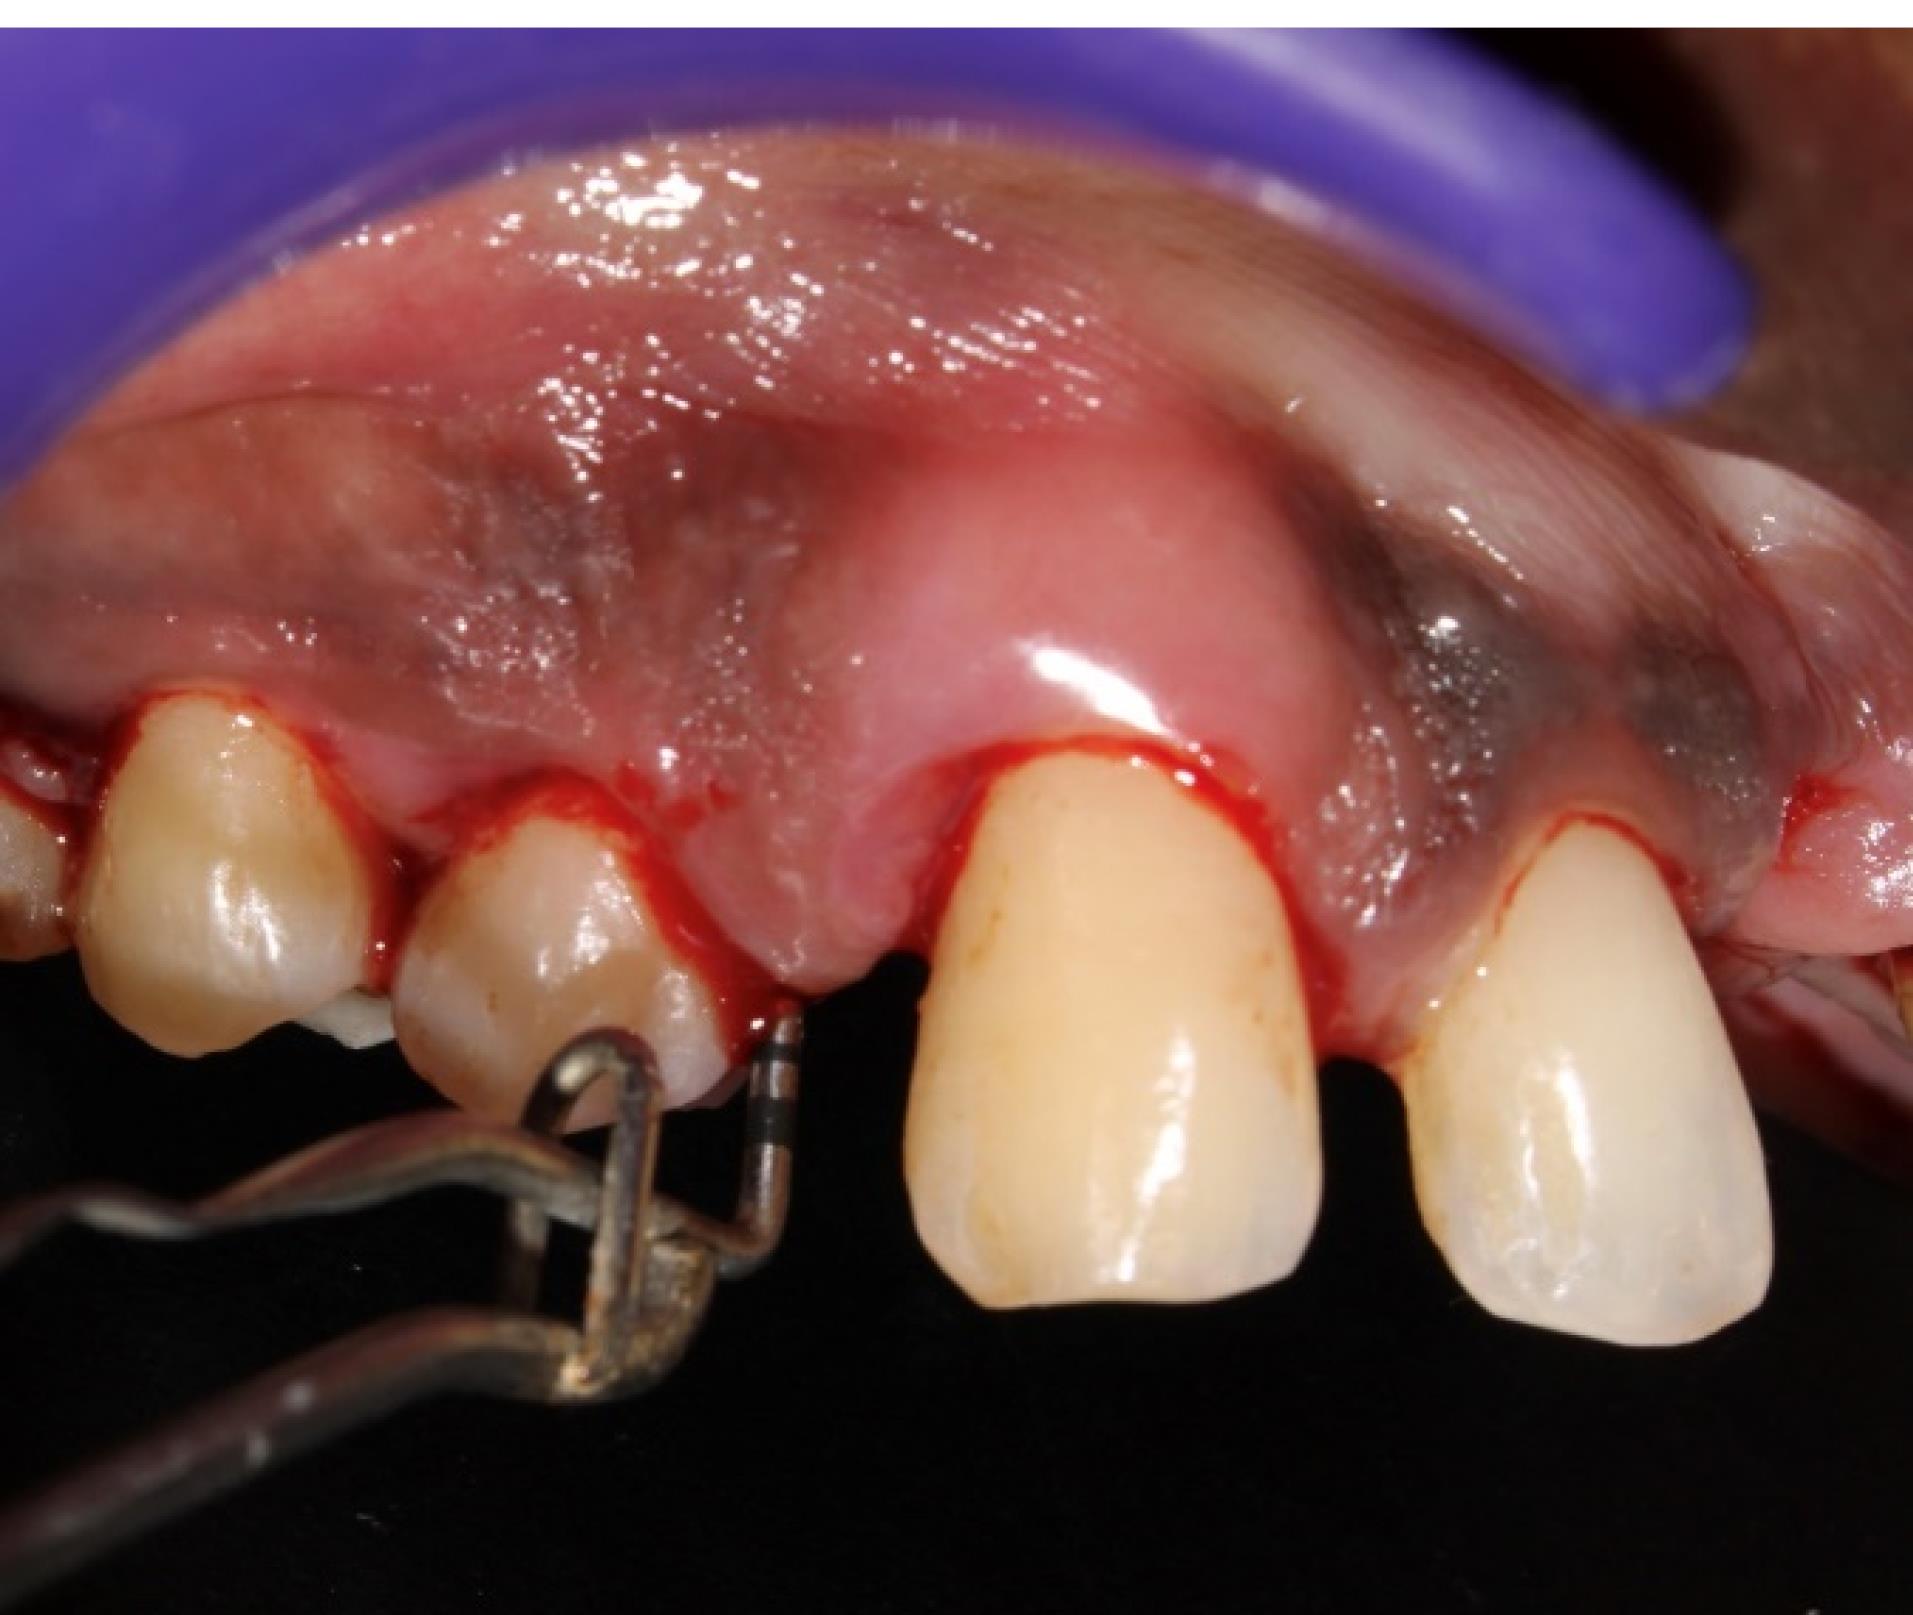

All the recruited subjects underwent the intervention (group 1 [n = 27], group 2 [n = 26], group 3 [n = 26]). During the follow-up, there were two dropouts from group 1 and one from each of the groups 2 and 3, resulting in 25 final samples in each group to be considered for final statistical analysis. No adverse reactions were observed during the study period for any of the interventions, and none of the participants reported any discomfort with the treatment protocol (Figures 5 and 6). The results are shown as mean ± standard deviation (SD) for clinical parameters and mean counts (log10) ± SD for microbiological parameters in Table 1 to Table 5.

Figure 6.

Postoperative picture (12th week) showing reduced PD in the experimental site (#5) shown in Figure 5 (group 1)